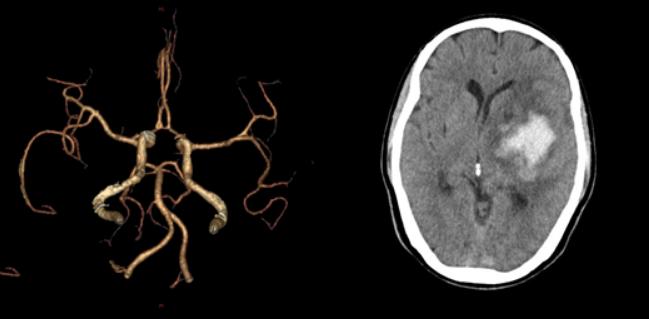

十八、脑出血合并开窗畸形

病例34:左侧基底节区脑出血合并右侧大脑前动脉A2段开窗畸形

病例35:右侧额叶急性脑出血合并左侧大脑中动脉M2段开窗畸形

病例36:左侧基底节区急性脑出血合并左侧椎动脉开窗畸形